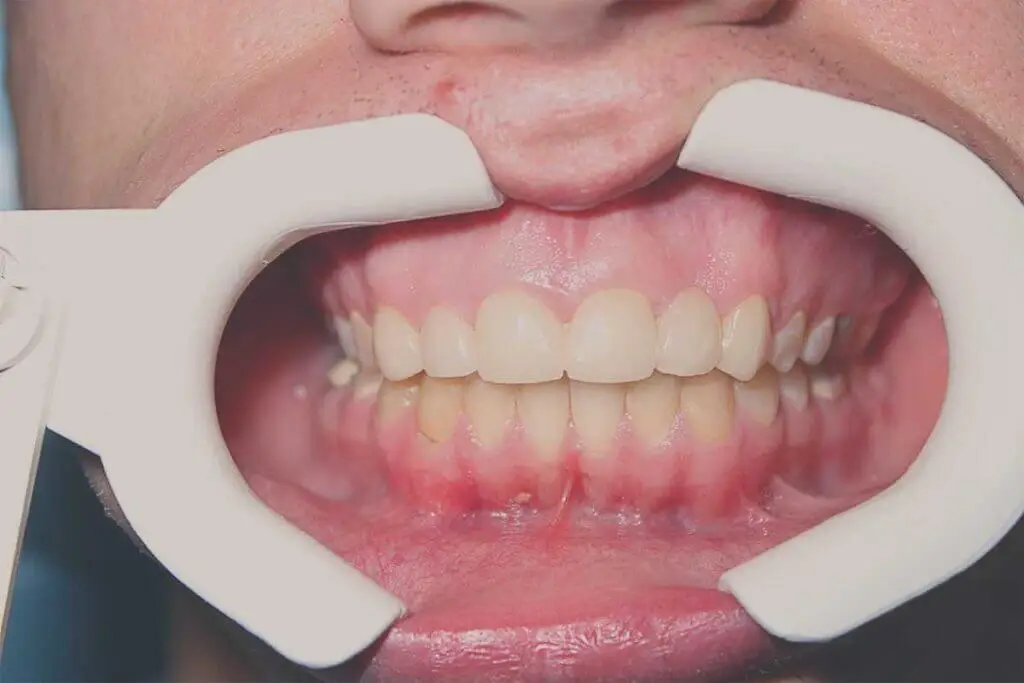

Róbert fiatal férfi páciens, tanuló. Komplex problémával keresett fel, diagnózisa során kiderült, hogy nyitott harapása mellett kétoldali keresztharapása is van, illetve bal felső második kismetsző fogát korábban eltávolították.

A kezelés során több lépcsőben oldottuk meg az eltérést, a fogszabályozó levétele után cirkon híddal pótoltuk a hiányzó fogat és a nagy kiterjedésű tömésekkel rendelkező front fogakat.